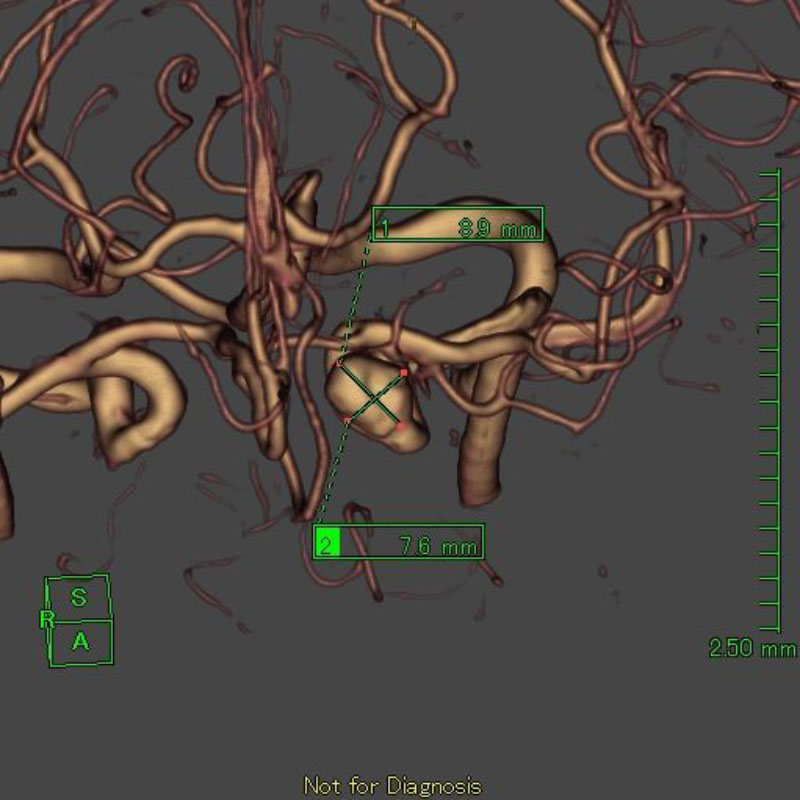

手術前

クリップ前

クリップ後